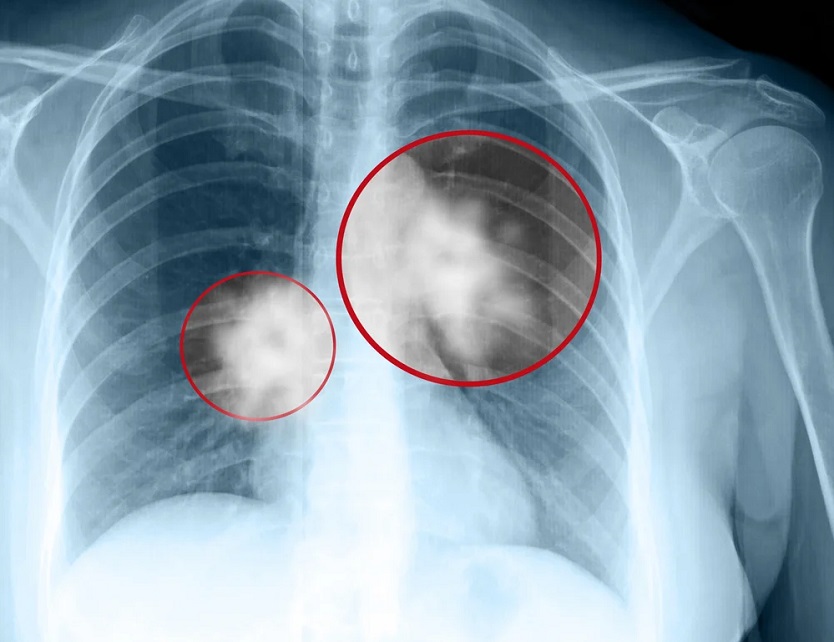

INCIDENȚA CANCERULUI PULMONAR ÎN JUDEȚ

Județul Hunedoara ocupă primul loc în zona de Vest a țării